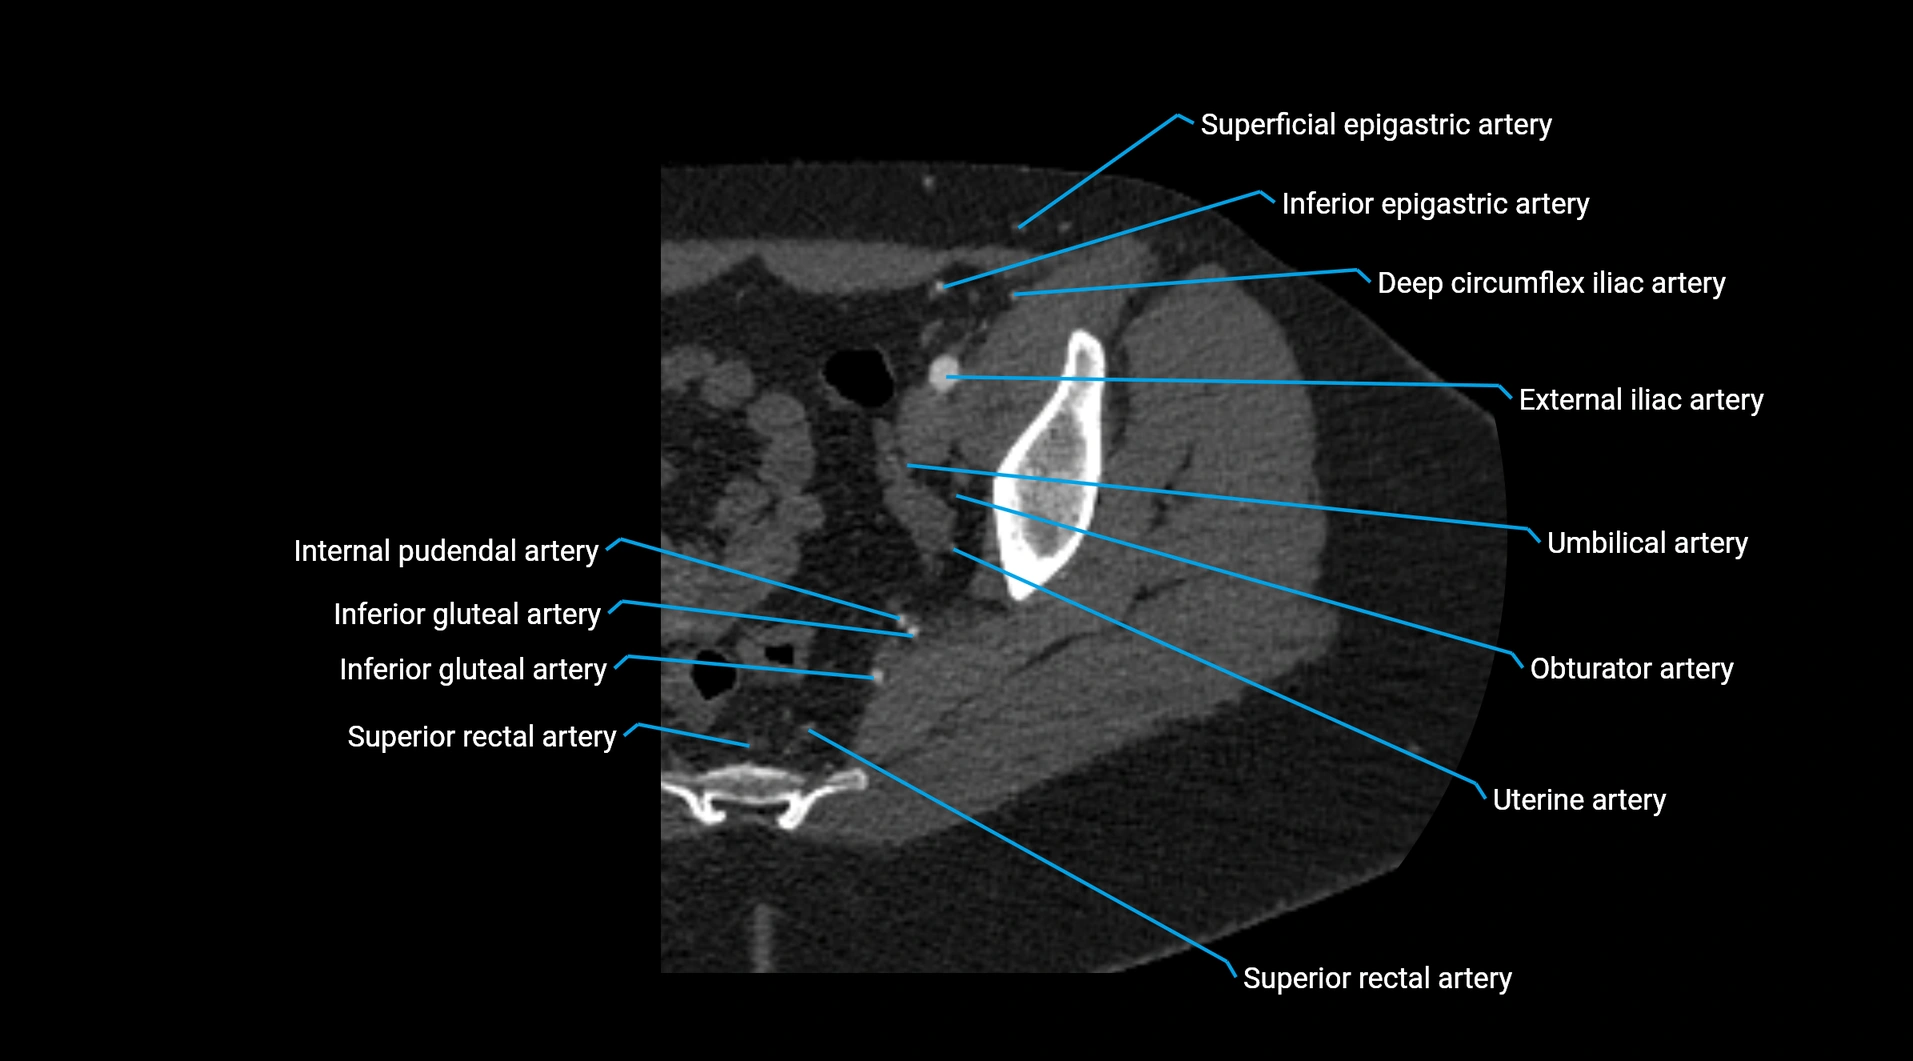

• Unpaired visceral branches: celiac trunk, superior mesenteric artery (SMA), inferior mesenteric artery (IMA)

• Paired visceral branches: middle suprarenal arteries, renal arteries, gonadal arteries (testicular or ovarian)

• Parietal branches: inferior phrenic arteries, lumbar arteries, median sacral artery

• Terminal branches: right and left common iliac arteries

Contrast-enhanced CT (CTA):

• Gold standard for abdominal aortic imaging

• Provides excellent detail of lumen, wall, aneurysm, thrombus, and branch vessels

• Multiplanar and 3D reconstructions help in aneurysm measurement, stent graft planning, and dissection evaluation